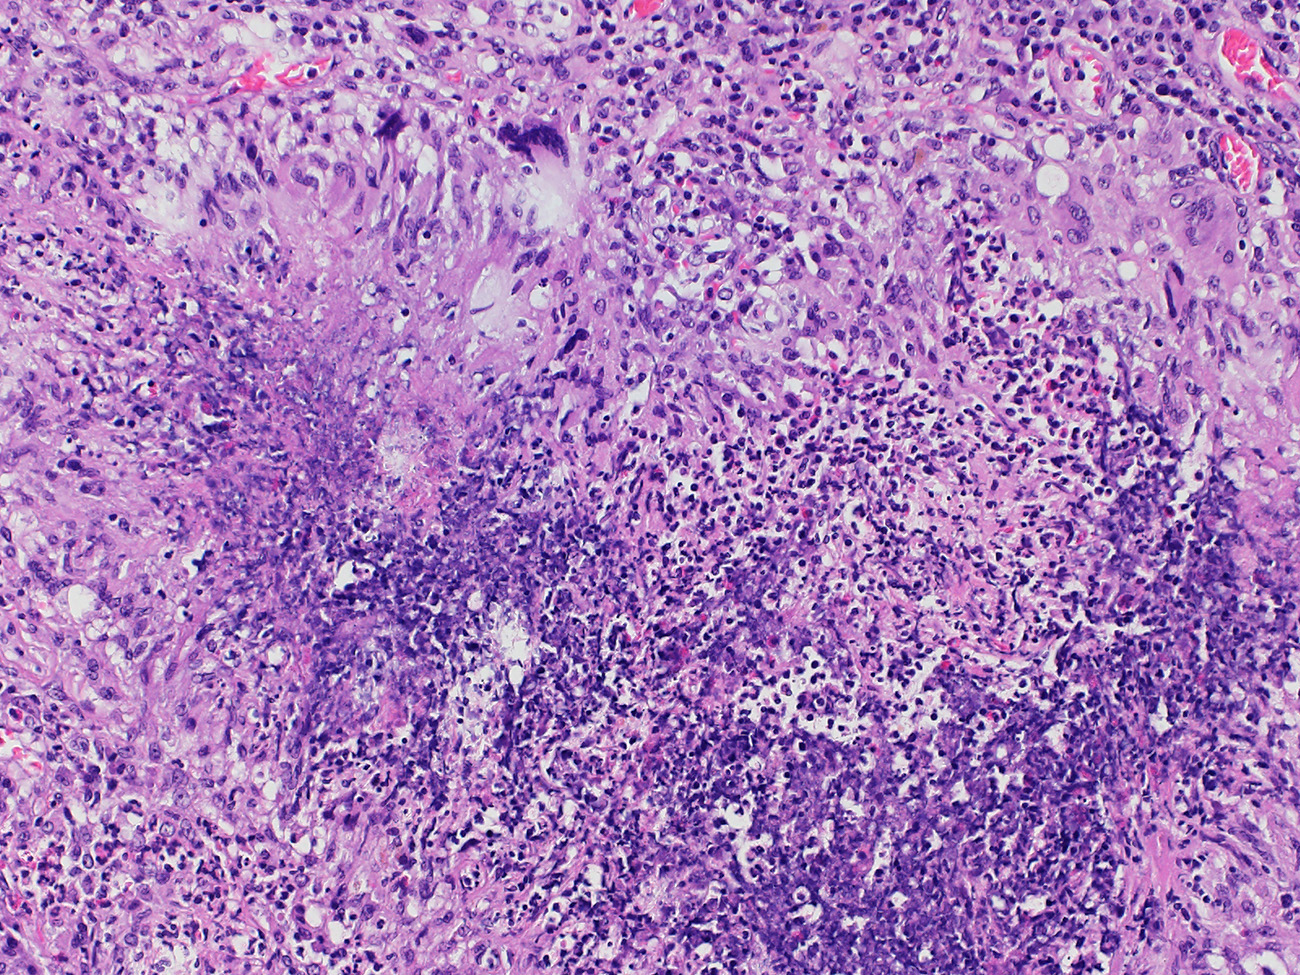

Granulomatose mit Polyangiitis (M. Wegener)

Basophile Nekrosen mit granulozytärem Detritus gesäumt von palisadierenden, teils mehrkernigen Makrophagen.

Geographische Nekrosen im Lungenparenchym und teils granulomatöse Entzündung. Vaskulitis.

Kein Nachweis säurefester Stäbchen mittels Ziehl-Neelsen-Färbung oder PCR. Stark erhöhte c-ANCA.

44 jährige Patientin mit Lungenkaverne bei Granulomatose mit Polyangiitis (M. Wegener)